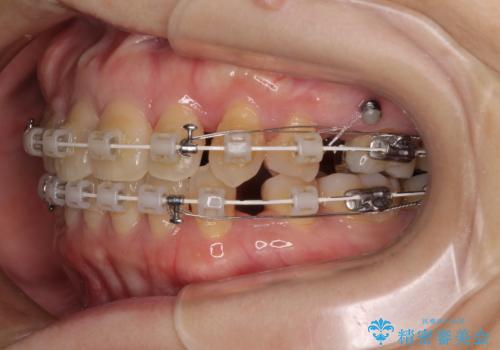

- 矯正装置

- 審美装置

- 前歯のデコボコと口元の突出感を気にして来院された患者様です。

上下前歯がくちばしのように突出していたため、上下左右の第一小臼歯4本を抜歯し、ワイヤー装置にて矯正治療を行うこととしました。

上顎骨に対して下顎骨がやや前方位に位置しているため、歯肉退縮を回避するために下顎前歯をあまり内側に移動させることができない状況でしたが、十分に口元の突出感を改善することができました。